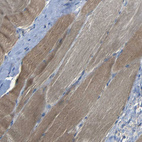

Immunohistochemical staining of human testis shows moderate granular cytoplasm positivity in leydig cells and cells in seminiferous ducts.